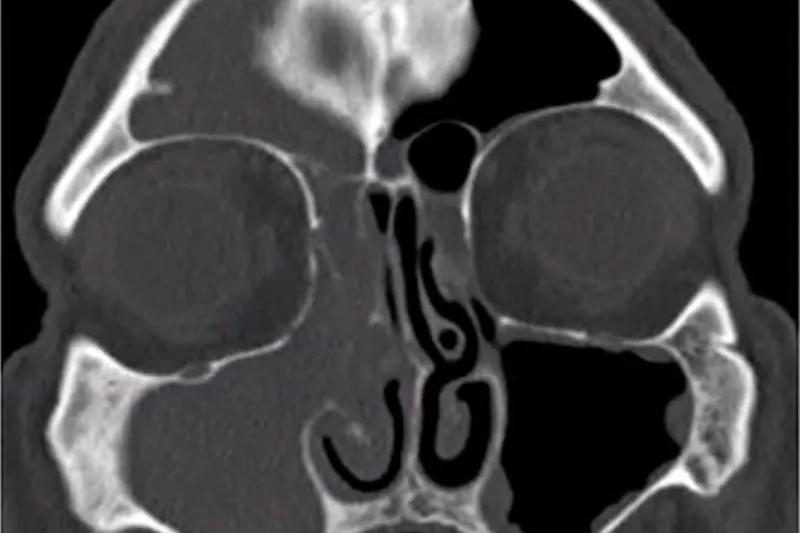

Rødderne på overkæbens præmolarer og molarer har tæt relation til bunden af sinus maxillaris, og derfor kan sygdomsprocesser eller behandlinger i disse områder føre til, at sinusbunden perforeres, så der opstår kommunikation mellem mundhulen og sinus.

3. Intraorale røntgenoptagelser. Periapikale optagelser af god kvalitet. Kan eventuelt i vanskelige tilfælde suppleres med panoramaoptagelse eller CBCT.